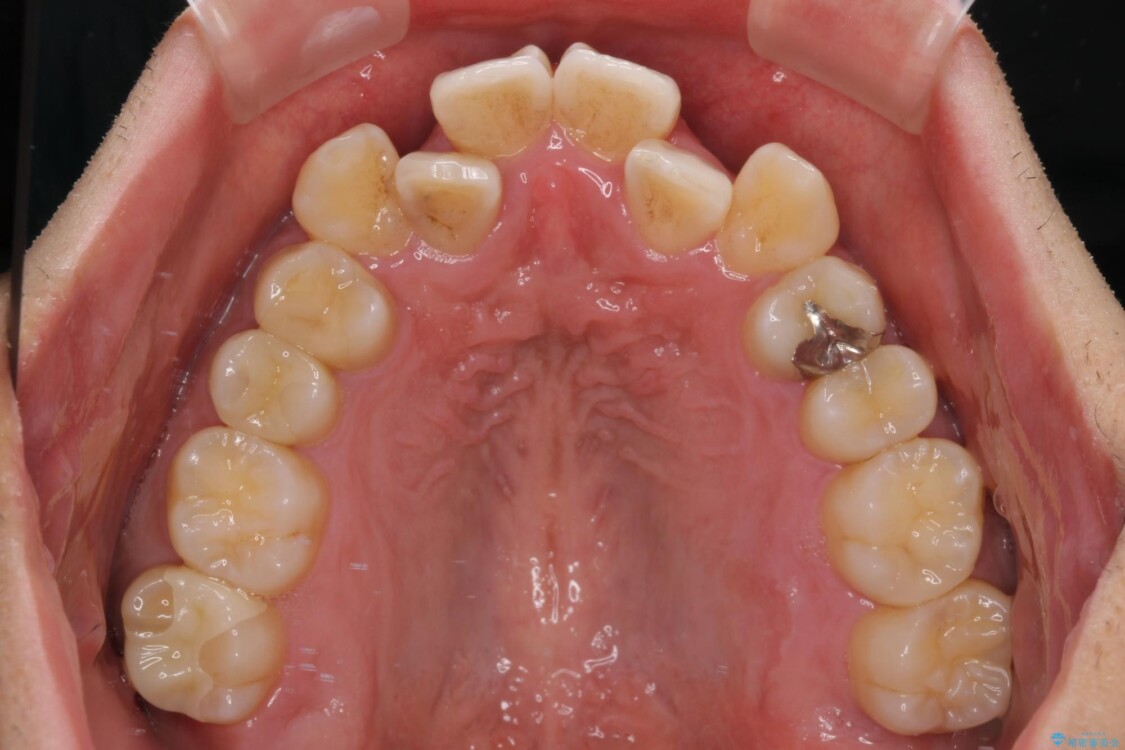

「八重歯を治したい」とご相談いただいた患者様の症例をご紹介します。

上下の前歯部に強い叢生(ガタガタの歯並び)があり、そのまま歯を並べると出っ歯になってしまう可能性がありました。

そこで、上下左右の第一小臼歯を抜歯し、歯が並ぶためのスペースを確保し叢生を解消する治療計画を立てました。

治療前

• 八重歯と前歯のガタガタを抜歯矯正で治療|クリアブラケット使用例 治療前画像